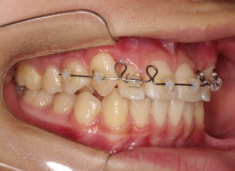

治療前

治療開始時